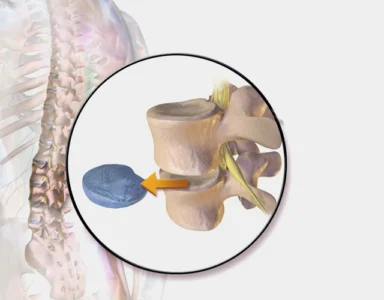

Discectomy

A discectomy removes a damaged or herniated disc. This disc puts pressure on the surrounding nerves. It causes pain, numbness, and discomfort. Removing the damaged part brings significant relief to the patient.

Microdiscectomy

Microdiscectomy is a minimally invasive version of discectomy. A smaller incision is made. Less muscle and tissue are disturbed. This means less pain and a faster recovery. It is one of the most preferred procedures after spine surgery consultations today.